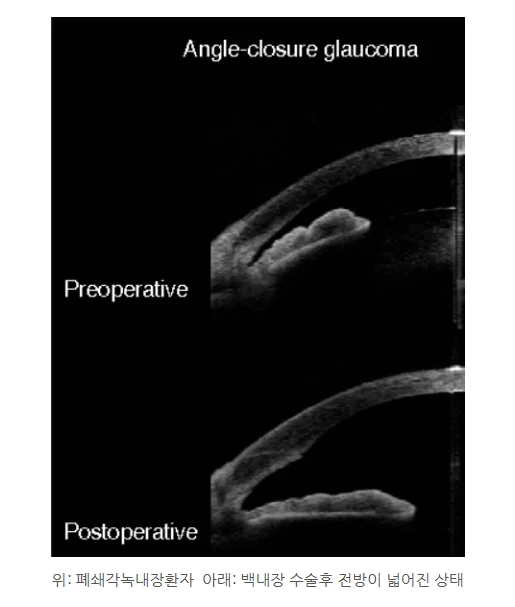

• 수술 중 난이도 증가: 폐쇄각 녹내장 환자의 경우 전방(수정체 앞쪽의 공간)이 일반인에 비해 매우 좁기 때문에 수술의 난이도가 올라가며 합병증의 빈도가 증가할 수 있습니다.

• 백내장 수술의 이점: 백내장 수술 시 혼탁해진 수정체를 제거하고 인공수정체를 삽입하게 되는데, 이 과정에서 눈 속 공간이 넓어지면서 안압이 감소하는 효과를 볼 수 있습니다. 특히 폐쇄각 녹내장 환자의 경우 안압이 높아지는 것이 위험하기 때문에, 백내장 수술을 통해 안압을 낮출 수 있다는 점이 큰 장점입니다.